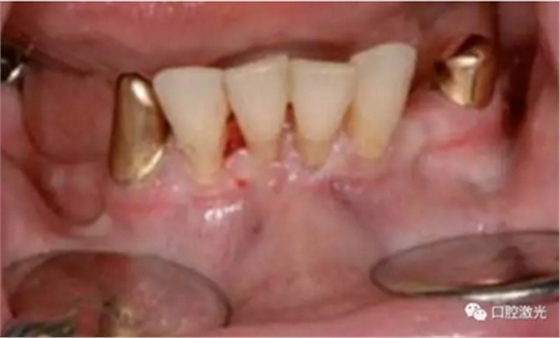

种植体暴露术术前

术中

愈合基台安装前

愈合基台安装后